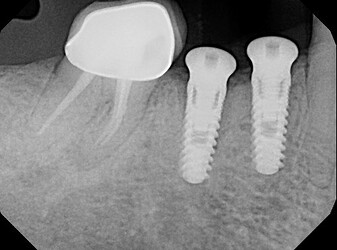

Buccal bone missing after implant placement

(preoperative picture for LL6), LL6 was extracted about 10 weeks before implant placement

Ossification is a complex and sometimes unpredictable process. I think 10 weeks is a too soon for implant placement since the extraction socket hasn’t fully calcified and you still have spongy bone inside the socket and psuedoperiosteum on the occlusal of the socket. I noticed radiographically i can see still see the socket. I usually enter and place implant at 4 months minimum post extraction, ideally 6 months, when radiographically the socket is mostly radiopaque indicating more calcification and ridge remodeled consistent to final dimensions.

I also noticed at implant placement i see 2 occlusal defects mesial and distal of the implant (most likely indicating mesial and distal root of previously extraction). which indicated the ridge is not fully ossified or calcified. i wonder if during osteotomy you felt soft bone instead of the usually hard mandibular bone. i think at implant placement you should have grafted. the occlusal is kind of flat, as if you did some occlusal reduction of some kind.

Your implant position is impeccable. good depth and orientation in the ridge.